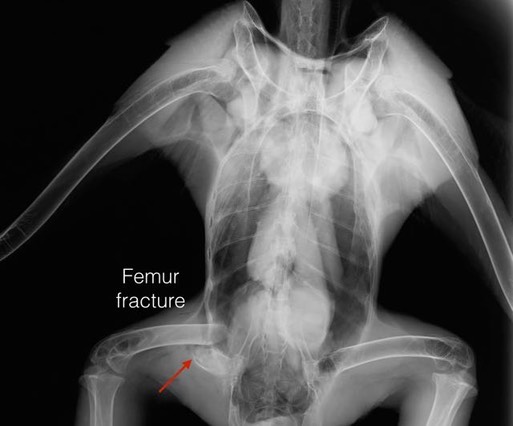

Bald Eagle 17-659

A juvenile Bald Eagle was found in an orchard near Eltopia, WA. The finders thought it had a broken wing and a broken leg. An exam confirmed the fractures. the mystery is they appear to have occurred at different times. The wing fractures look old. There is significant callus formation and the fractures appear to have been caused by gunshot. The leg fracture appears to be very recent and shows no sign of being caused by gunshot. Unfortunately the damage was too extensive to be successfully repaired, and the bird was euthanized.